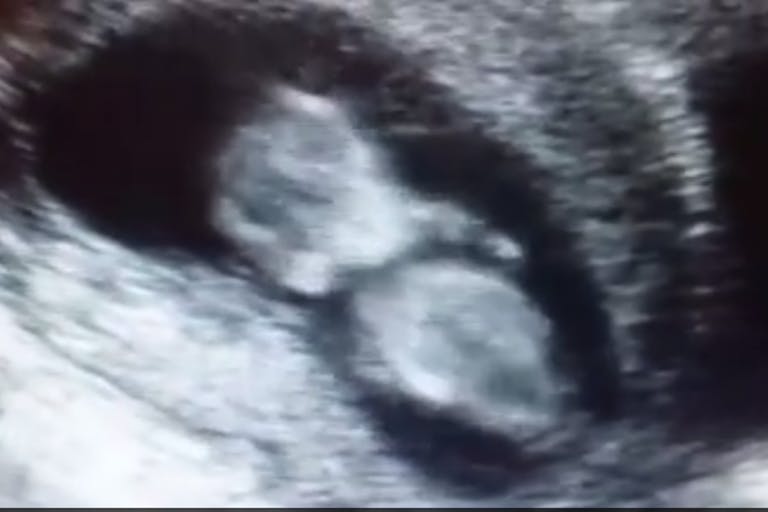

A beautiful video of a baby in utero is rapidly being shared across social media. The ultrasound shows the 11-week, 4-day-old preborn child bouncing around in the womb. This child is still in the first trimester, the gestational age during which most abortions take place.

Monica Barba posted the video, saying, “For everyone who is wondering what can be seen on an ultrasound of a 1st trimester baby. Enjoy!” She says the child belongs to a woman who came into the pregnancy resource center and chose life. Barba describes the child as having a lot of energy and being full of life, and that another ultrasound later revealed he is a boy.

At 11 weeks gestation, preborn babies are rapidly growing. Not only do they have beating hearts, but hands and feet, fingers and toes, tongues and palates, and hair follicles forming on their heads. Babies at this stage can do somersaults, forward rolls, stretches— and as this baby shows, jumps.